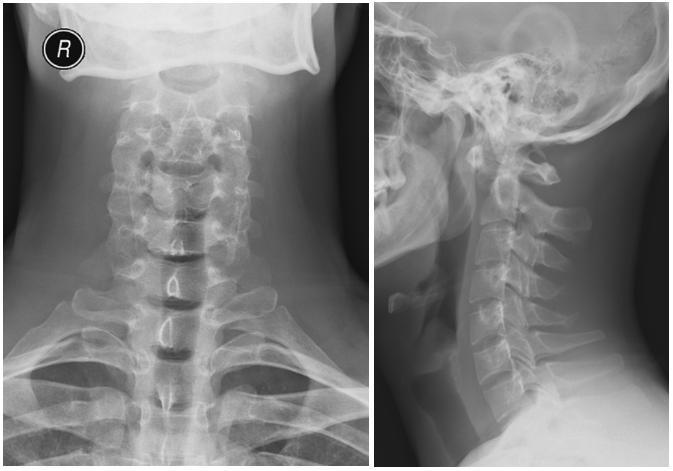

A 27-year-old male patient with no relevant medical or surgical history and working in the military army, was observed in an Orthopedics consultation, referred from primary health care for complaints of neck pain, without irradiation to the upper limbs, associated with limitation of mobility, especially in sagittal plane movements, with 4 months of evolution (Neck Disability Index (NDI) of 26). The patient denied a history of trauma, but reported upper respiratory infection (pharyngitis) one month before the onset of cervical pain. Physical examination revealed decreased cervical mobility, without other major findings. The diagnostic study began with two-plane cervical radiography (Figure 1), with an approximate ADI value of 10.5 mm, as well as dynamic radiographs (Figure 2), which demonstrated C1-C2 dynamic instability (ADI of 10.9 and 9.8 mm respectively). The CT study confirmed atlanto-axial sub dislocation and excluded the presence of fractures or facet subluxations (Figure 3). The study was complemented by magnetic resonance imaging, which confirmed atlanto-axial sub dislocation, associated with inflammation and thickening of the paravertebral soft tissues, with transverse ligament incompetence (Figure 4 - magnetic resonance imaging). Due to the decreased mobility of the upper cervical spine, the possibility of Meningitis was raised. Blood analytical study showed marginal elevation of C-Reactive Protein (28 mg/L), thus, the hypothesis of Grisel's Syndrome was placed. The patient was initially treated with the use of a Minerva cervical collar and broad-spectrum empirical antibiotic therapy with Ceftriaxone for 6 weeks, but after this period, there was unfavorable clinical evolution, with worsening of cervical pain and functional status (NDI of 30). Surgical treatment was therefore elected, through posterior atlanto-axial fixation, which is in accordance with other cases published in the literature.2The surgery was uneventful and the patient had a favorable clinical course, with significant improvement in neck pain and joint mobility, with an improvement in the NDI from 30 to 5. Radio graphically, a reduction in atlanto-axial subluxation was confirmed (Figure 5), which remained stable until 5 years of follow-up. There were no late complications and the patient resumed his normal activities.

Figure 1 Initial radiografic study.